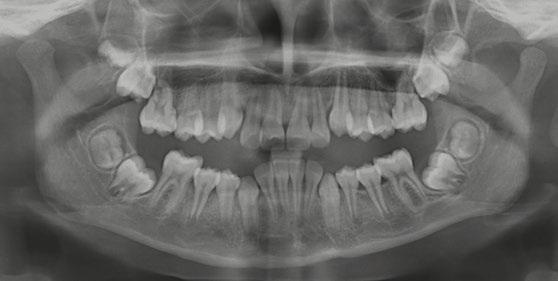

En la ortopantomografía se aprecia una dentición permanente a falta de la erupción de los 2os y 3 os molares, así como una asimetría ósea con rama y cóndilo mandibular izquierdo menos desarrollado (figura 9), causante de la asimetría facial descrita anteriormente.

Figuras 9-11.

Ramos-Ríos y cols. estudiaron dos escuelas con niños de rango de edad de 6 y 12 años, en México. Para ello, se empleó un cuestionario para los padres y se obtuvo que un 6,84% padecían asma; de éstos se llevó a cabo el estudio (Tabla 1).

Tras los resultados obtenidos llegaron a la conclusión de que son muchas las patologías asociadas al asma, y no solo repercusiones sobre su salud oral, sino maloclusiones del tipo mordida abierta o paladar ojival asociadas a deglución atípica, propias de una respiración oral

Castañeda-Zetina y cols. realizaron un estudio para comparar las maloclusiones en niños asmáticos y sanos, en el cual se incluyeron 186 pacientes de entre 5 y 12 años. Los resultados obtenidos fueron que más del 50% de los niños asmáticos tienen respiración oral. Las principales alteraciones oclusales presentadas eran mordida abierta anterior y mordida cruzada posterior, menos frecuente; además de una menor frecuencia de clase III, solo un 11,6%, ya que el cambio postural de estos pacientes favorece la entrada del aire inclinando la cabeza hacia atrás y favoreciendo la aparición de clase II al posterorrotar la mandíbula. Estas modificaciones posturales van a producir alteraciones maxilares y desequilibrio en los m ú sculos periorales; por ello, su detección precoz ayudará a resolver el problema con un abordaje multidisciplinario y dando armonía al complejo dentoesquelético (56).